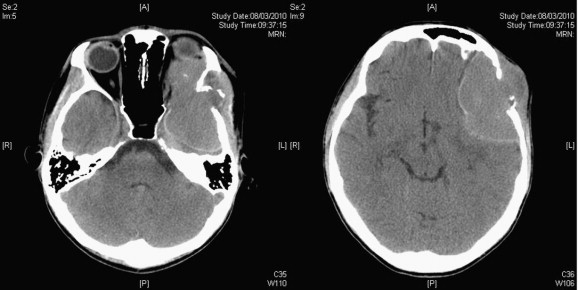

He then complained of left facial numbness and diplopia in February 2010. There was facial asymmetry and his left eye protruded. There was a bulge over the left temporal fossa that was firm and nontender. The overlying skin looked normal. He had diplopia in all gaze but no ophthalmoplegia. There was numbness over the maxillary branch of the left trigeminal nerve. The visual acuities of the right and left eyes were 20/20 and 20/25, respectively, but he complained that the image from the left eye was significantly dimmer. Visual fields of both eyes were full. Magnetic resonance imaging (MRI) showed a 5 cm contrast enhanced lesion over the left temporal region with extension into the left orbit displacing the globe. CT scan showed that the left orbital roof and part of the left temporal bone were eroded by the tumor (Fig. 1). There was also midline shift.

(Left) Preoperative plain computed tomography of the brain showed tumor ...

Figure 1.

(Left) Preoperative plain computed tomography of the brain showed tumor extending into the orbit with the eyeball displaced and (Right) involved the left temporal region.